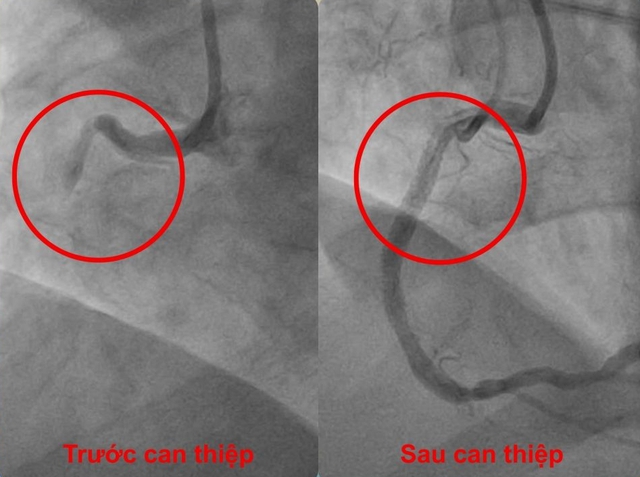

Hình ảnh trước và sau can thiệp

Ngay sau đó, bệnh nhân được chuyển đến phòng can thiệp tim mạch. Kết quả chụp mạch vành cho thấy tắc hoàn toàn đoạn gần động mạch vành phải. Các bác sĩ nhanh chóng tiến hành nong mạch và đặt stent, giúp tái thông hoàn toàn dòng máu nuôi tim.